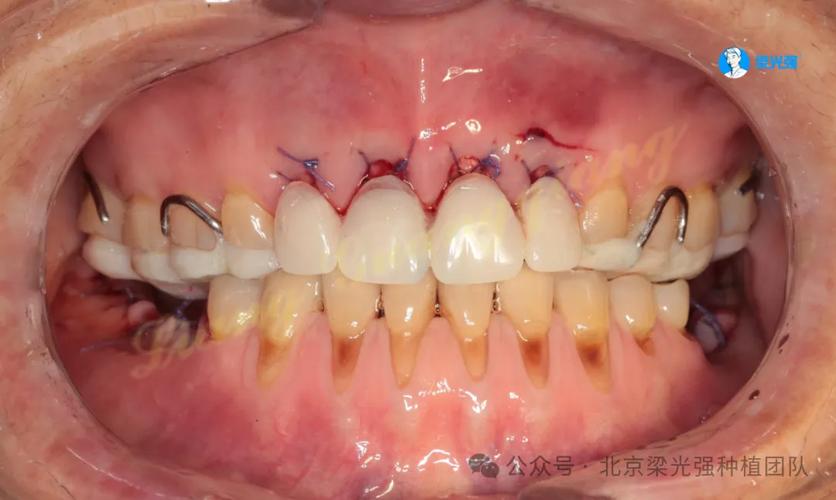

创伤牙合的临床表现多样,可涉及牙齿、牙周、牙体及周围组织,具体症状因创伤程度和持续时间而异,牙齿敏感与疼痛是最常见的早期症状,患者常在咀嚼或咬合时出现尖锐疼痛,对冷热刺激敏感,甚至出现自发痛,这可能是由于异常咬合力导致牙本质小管暴露或牙周组织受压,引发牙髓充血或炎症,牙周组织方面,创伤牙合初期可表现为牙龈红肿、探诊出血,若未及时干预,可能发展为牙周袋加深、牙槽骨吸收(可见 X 线片牙槽骨嵴高度降低),严重时甚至出现牙龈退缩、牙根暴露,牙齿松动度增加(Ⅲ度松动时需警惕牙根吸收或牙周不可逆损伤),牙体组织也可能受累,如咬合力集中在某颗牙时,可能导致牙冠出现裂纹或折裂,或修复体(如已有充填体)脱落;长期创伤还可能引发牙根吸收,表现为牙根长度缩短(X 线片可见牙根轮廓不规则),部分患者可能出现颞下颌关节(TMJ)症状,如关节区疼痛、弹响、开口受限等,这是由于咬合紊乱导致下颌运动轨迹异常,长期负荷过重所致。

为更直观展示创伤牙合的临床表现,可将其按受累组织分类如下表: